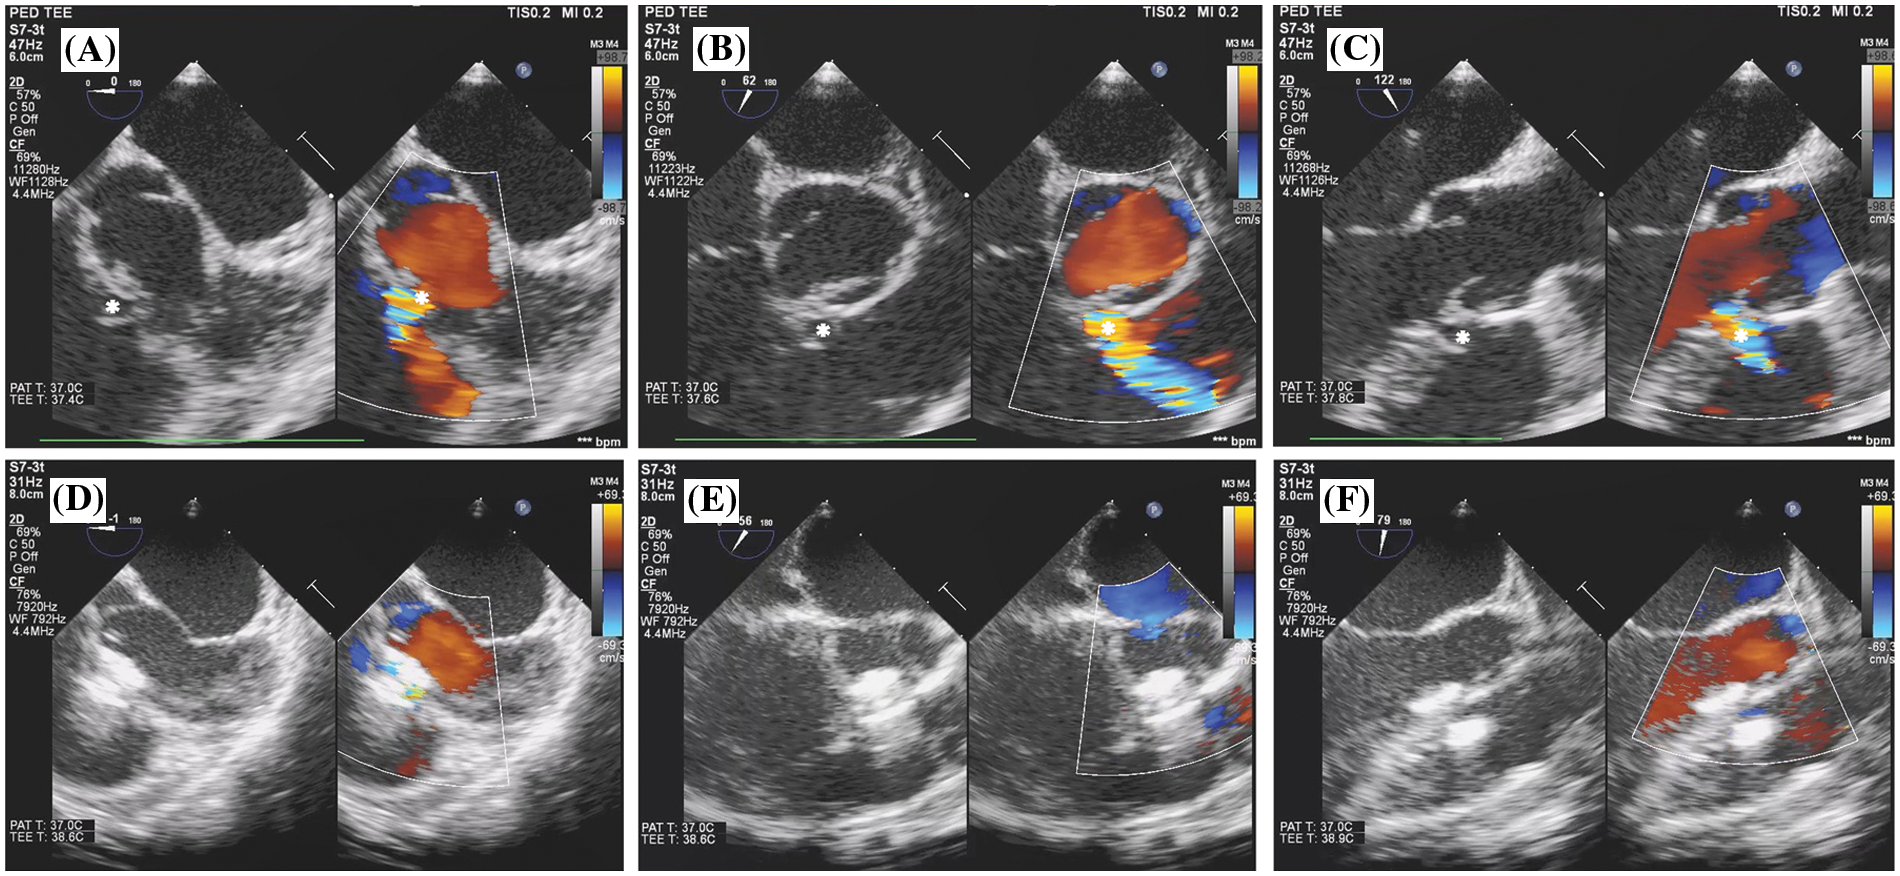

Figure 3: Transoesophageal echocardiogram findings of antegrade OVSD closure. (A), (B), and (C) show OVSD (*) in 0°, 60°, and 120° of the mid-oesophageal view before device implantation. (D), (E), and (F) show OVSD in 0°, 60°, and 120° of the mid-oesophageal view after device implantation

Complete closure rate was not significantly different between transcatheter and surgical cases immediate and 12 months after the procedures. (80% and 88% vs. 92% and 96%; p > 0.05). The severity of AR after transcatheter OVSD closure remained unchanged in most patients (80%). Nonetheless, AR increased in 4 cases (16%) and disappeared in 1 case (4%) whilst in the surgical group, AR remained unchanged in 15 cases (60%), increased in 3 cases (12%), and disappeared in 7 cases (28%). The AR severity immediate and 12 months after the treatments were not significantly different between the groups. Furthermore, new onset or worsening of AR was not significantly different (p = 1) (Figs. 5 and 6).